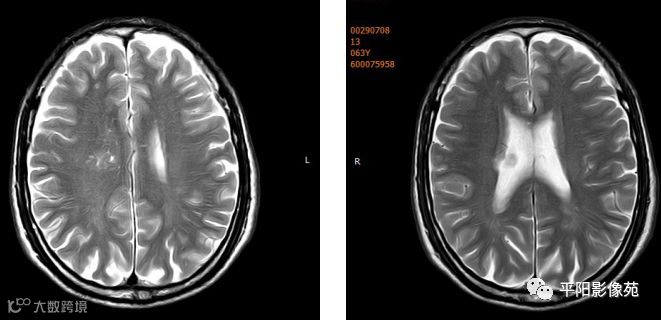

右侧额叶中央前回局部脑裂增宽,并向内延伸,周围衬以等灰质信号,呈稍长T1稍长T2信号,病灶自软脑膜向内延伸,与室管膜相连。